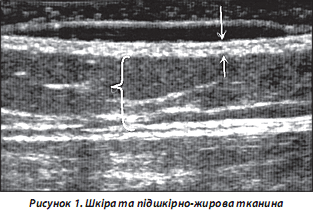

1. Шкіра та підшкірна жирова клітковина. Найкраще візуалізується при скануванні високочастотними датчиками (від 12,5 МГц) у вигляді гіперехогенної відносно гомогенної ділянки з різною товщиною, що залежить від локалізації ділянки, яка сканується, віку та статі хворих. Зазначимо, що в чоловіків товщина шкіри більша, ніж у жінок. Шари шкіри (епідерміс та дерма) практично не диференціюються при проведенні УЗД (рис. 1).